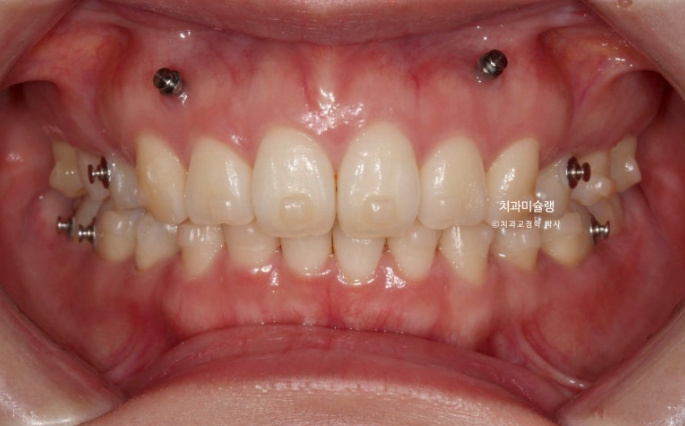

26.01

이제 전후 비교 보겠습니다.

총 치료기간은 3년 2개월, 재제작은 3회 했습니다.

어금니 교합은 뜨는 곳 없이 좋습니다.

앞니 각도는 적절하며

입술 부전증이 해소가 되어 이제 비로소 입이 편하게 다물립니다

예쁜 입매가 완성되었습니다.

상악골 과잉이 심한 골격에서 교정으로 위턱뼈가 들어가는 것은 아니지만 최소한 위 앞니는 교정으로 예쁘게 넣어줄 수 있습니다.

아래 앞니는 계획대로 뒤로 1mm도 뒤로 들어감 없이 잘 유지가 되었고 위 앞니는 치조골이 허용하는 범위 내에서 아래앞니와 만나기 위해 최대한 뒤로 들어갔습니다.